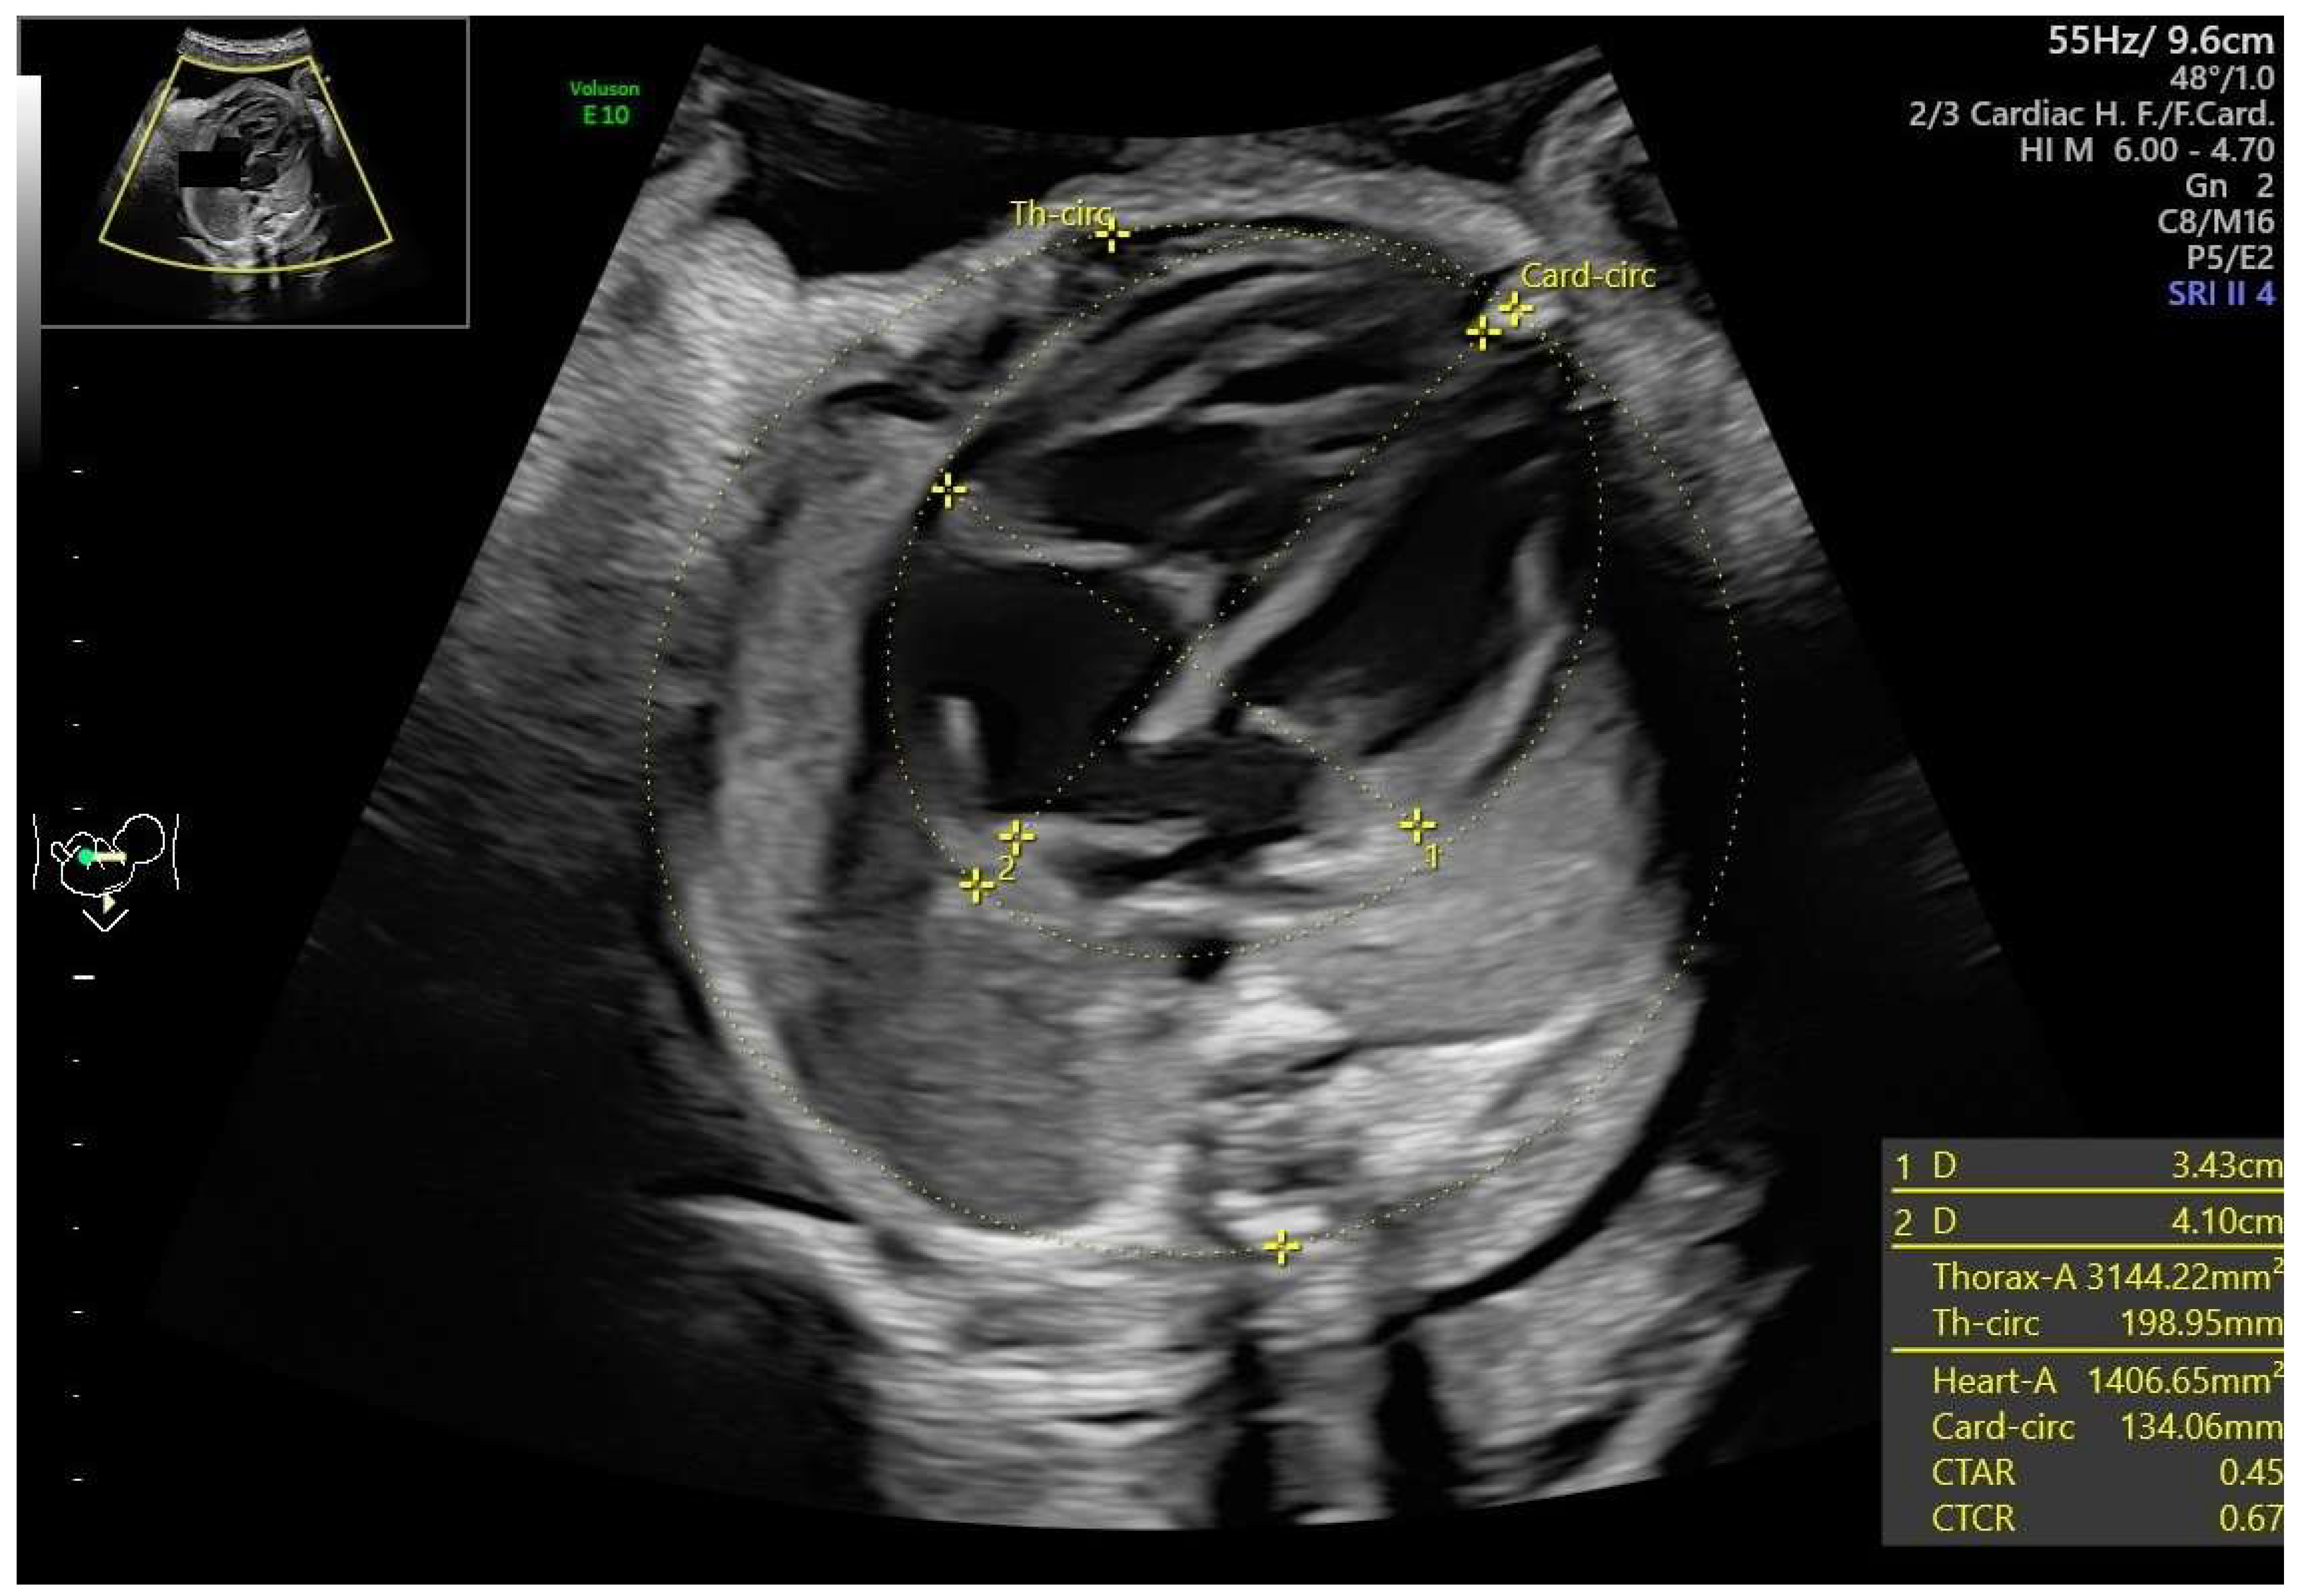

- Ductal constriction (DC), defined as a peak systolic velocity (PSV) > 1.4 m/s or >95th percentile for gestational age, a peak diastolic velocity > 35 cm/s or >95th percentile, or a pulsatility index (PI) < 1.9 [8,9]. The measurement was taken by visualizing the DA at the 12th or 6th “hour” (+/− 30 degrees), which was performed by seeing the ductal arch in the long-axis view. Fetal slow movements or hiccups were accounted for and if they occurred the measurement was taken more times during the examination (Figure 2).

- Sylwestrzak, O.; Respondek-Liberska, M. Echocardiographic Methods of Fetal Heart Size Assessmentheart to Chest Area Ratio and Transversal Heart Diameter. Prenat. Cardiol. 2018, 8, 20–23. [Google Scholar] [CrossRef]

- Respondek, M.; Respondek, A.; Huhta, J.C.; Wilczynski, J. 2D echocardiographic assessment of the fetal heart size in the 2nd and 3rd trimester of uncomplicated pregnancy. Eur. J. Obstet. Gynecol. Reprod. Biol. 1992, 44, 185–188. [Google Scholar] [CrossRef]